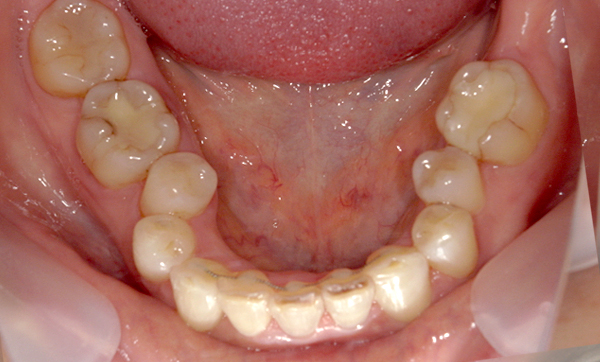

症例_016 上下顎の部分矯正

治療期間:8ヶ月金額:48万円+税50代女性八重歯捻転歯前歯のガタガタ